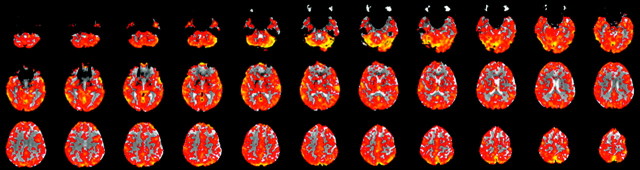

All subjects showed strong and qualitatively symmetric BOLD signal intensity increases during hypercapnia. Significant responses were not limited to brain parenchyma with high z-scores in both gray matter and the subarachnoid spaces and lower z-values in white matter voxels with a clearly visible interface between gray and white matter (Fig 3). As expected, absolute PSC were higher for gray matter than with white matter (Table 1).

Fig 3.

A CO2 reactivity map of a healthy volunteer showing symmetric hemispheric signal intensity change after stimulation with CO2. This is a contrast map denoting magnitude of signal intensity change.